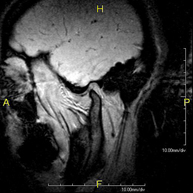

RM ATM (Articulación Temporo-Mandibular)Prueba diagnóstica no invasiva que consiste en la obtención de imágenes de alta definición anatómica de las articulaciones témporo-mandibulares mediante el empleo de un campo electromagnético y ondas de radio (con un emisor y un receptor). No utiliza radiación ionizante. Se realiza un estudio funcional de las ATM, en las distintas fases de apertura y cierre de la boca. Indicaciones: dolor, bloqueo de la articulación y ruidos durante la masticación.